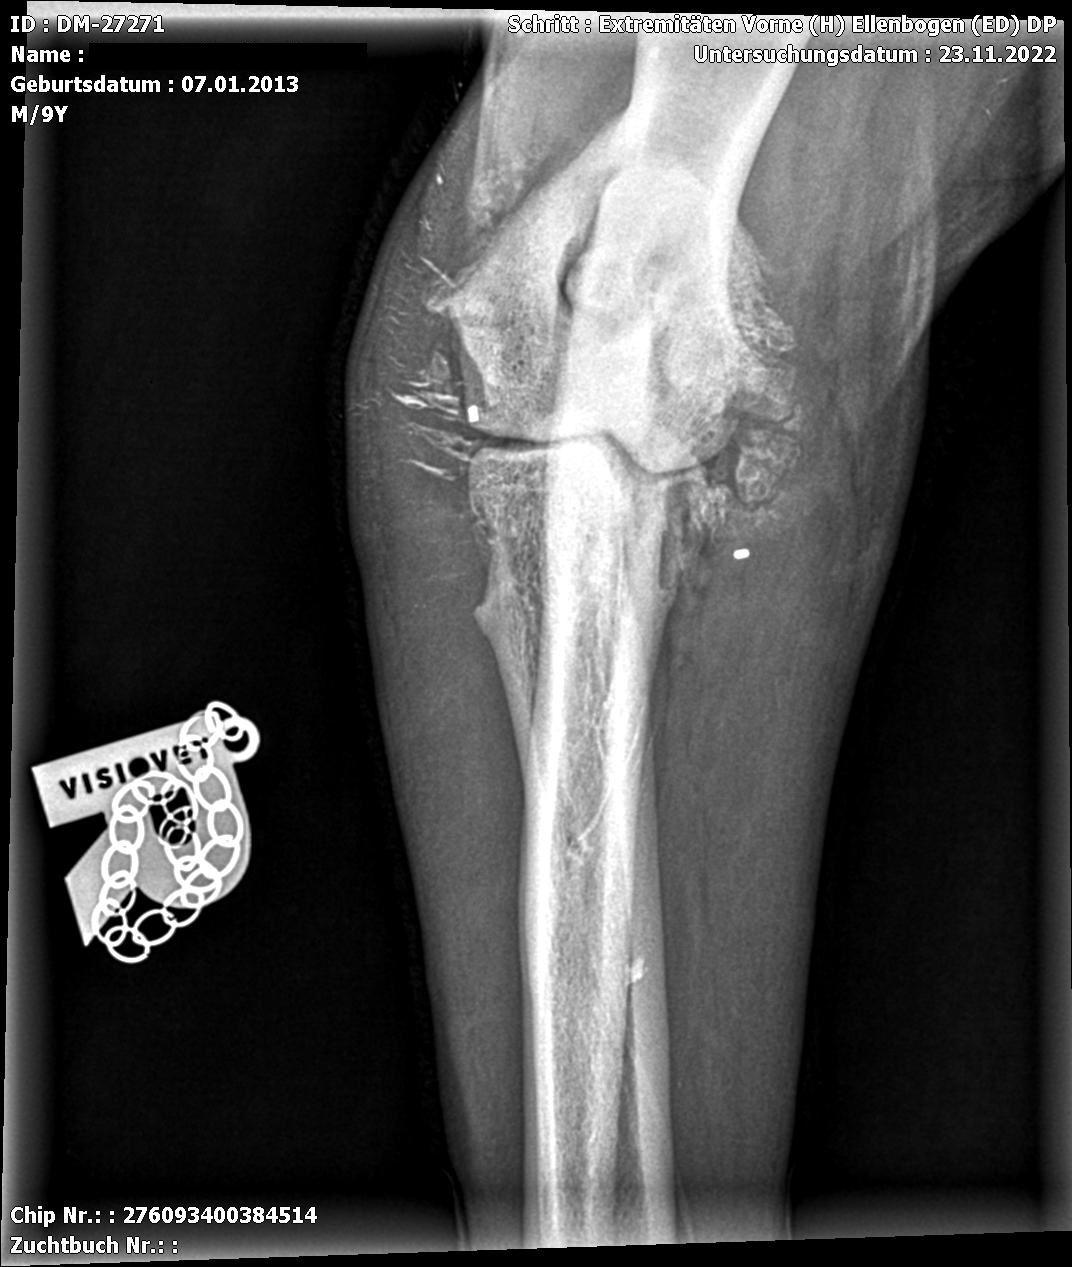

Die Ellbogendysplasie ist die häufigste Entwicklungsstörung des Ellbogengelenks bei juvenilen und erwachsenen Hunden mittelgroßer und großer Rassen und verursacht oftmals eine Lahmheit der Vordergliedmaßen. Viele Rassen (Labradore etwa) haben eine genetische Veranlagung, eine Ellenbogengelenksdysplasie zu entwickeln.

Diese Erkrankungen können sich isoliert oder in Kombination präsentieren. Jede Form der Ellbogendysplasie kann eine irreversible Osteoarthrose (OA) des Gelenks durch Knochen- und Knorpelläsionen, Instabilität und chronische Synovitis hervorrufen. Die Ellbogendysplasie des Hundes wird als eine polygenetische Erkrankung beurteilt, wobei Umgebungsfaktoren und genetische Faktoren bei der Entwicklung der Läsionen eine entscheidende Rolle spielen

Die Coronoiderkrankung ist die am häufigsten vorkommende Form des Ellbogendysplasie-Komplexes. Die Symptome können initial subklinisch sein, sich aber auf Dauer als deutliche Lahmheit manifestieren. Die Coronoiderkrankung ist, wie viele Gelenksläsionen, durch eine progressive Osteoarthrose charakterisiert.

Die Coronoiderkrankung ist unter den verschiedenen Formen der der Ellenbogengelenksdysplasie die häufigste Ausprägung der Erkrankung.

Eine gründliche Diagnostik hilft die Erkrankung zu diagnostizieren und die Schädigung des Gelenkes umfassend zu analysieren. Hier hilft uns unser CT und die Arthroskopie. Zur abschließenden Diagnostik und vor allem Therapie hat sich die Arthroskopie international als Goldstandard durchgesetzt. Sie ermöglicht eine direkte Beurteilung von Knochen und Gelenkknorpel. Wir operieren bereits seit 2004 Gelenke arthroskopisch.